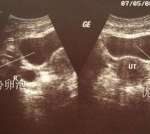

大促方案是标准的促排卵方案,是在月经来潮第二天开始服用促排卵药物,促使多个卵泡同时发育成熟,为后续环节奠定基础。大促方案因用药时间短、促排效果好、便于实时进行卵泡监测和用药跟踪,被俄罗斯广泛应用于临床实践中。

抗结剂方案也属于大促方案,也是在月经来潮第二天开始服用促排卵药,不同的是该方案在促排用药的第5或第6天使用拮抗剂药物(一种保卵针),可以有效防止卵巢过度刺激,防止卵泡过早排出去。